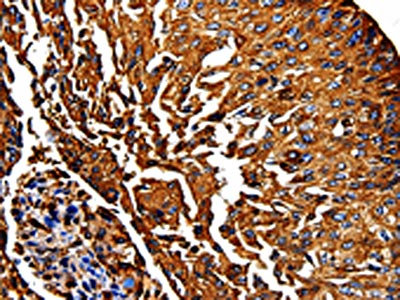

The image on the left is immunohistochemistry of paraffin-embedded Human lung cancer tissue using CSB-PA057752(PKM Antibody) at dilution 1/50, on the right is treated with fusion protein. (Original magnification: ×200)